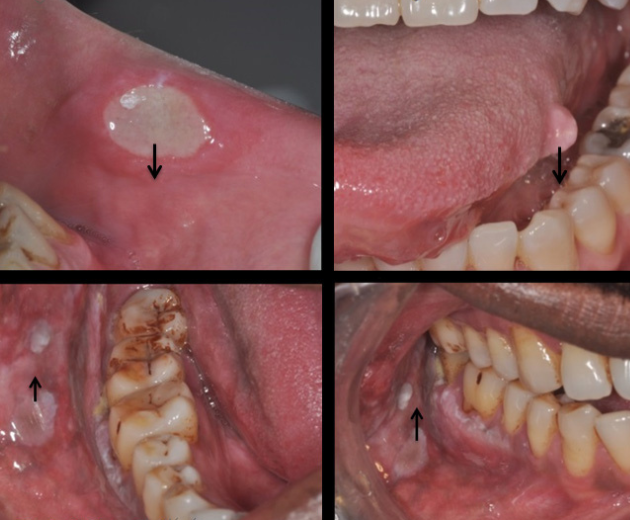

Oral cancer screening is a preventive examination where a dentist checks for signs of cancerous or precancerous conditions in the mouth. It includes inspecting the lips, tongue, cheeks, gums, throat, and other oral tissues for any unusual changes.

Persistent mouth sores or ulcers

White or red patches on the tongue or gums

Lumps, swelling, or thickening of oral tissues